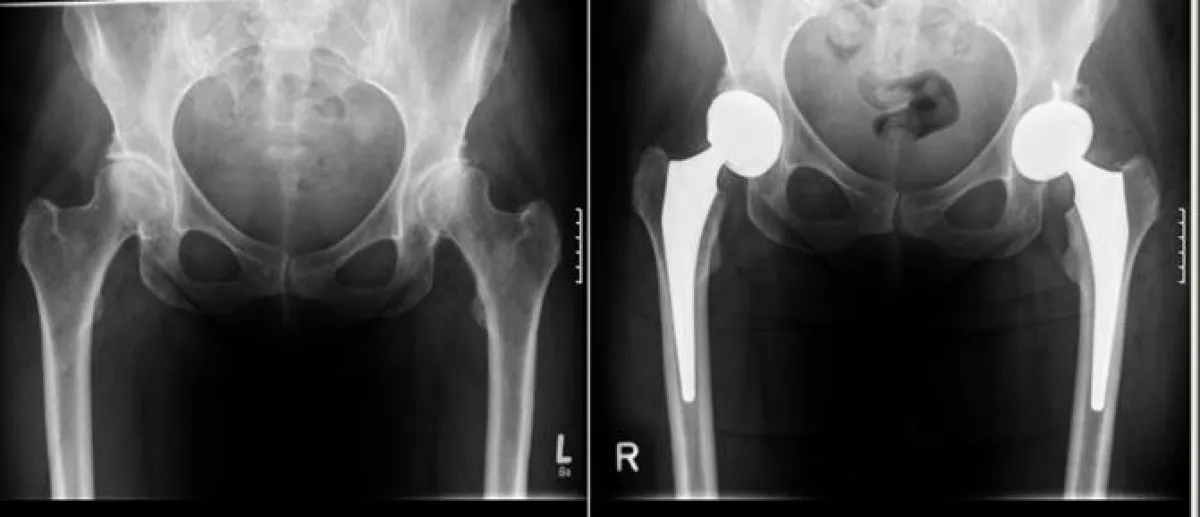

Dr. med. Klaus Kolb ist Chefarzt der Klinik für Unfallchirurgie, Orthopädie und Sportmedizin. Hier werden jährlich mehr als 400 Prothesen an Hüfte und Knie eingesetzt. Die Operateure verfügen dabei über eine jahrelange Erfahrung auch in minimalinvasiven Verfahren für eine größtmögliche Schonung des umgebenden Gewebes. In seinem Vortrag wird Dr. med. Kolb über neue Implantate und Erkenntnisse berichten, die zu deutlich verbesserten Ergebnissen führen. Während bei jüngeren Patienten eher die Leistungsfähigkeit im Vordergrund steht, richtet sich das Behandlungsziel bei älteren Patienten stärker auf die Schmerzreduktion und den Erhalt der Mobilität im gewohnten sozialen Umfeld. Dazu gehören auch Vorkehrungen, um die gewonnene Verbesserung Zuhause zu erhalten.